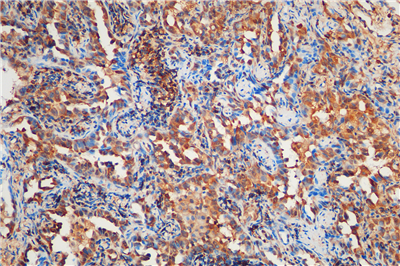

免疫組化是應(yīng)用免疫學(xué)基本原理——抗原抗體反應(yīng),即抗原與抗體特異性結(jié)合的原理,通過(guò)化學(xué)反應(yīng)使標(biāo)記抗體的顯色劑(熒光素、酶、金屬離子、同位素) 顯色來(lái)確定組織細(xì)胞內(nèi)抗原(多肽和蛋白質(zhì)),對(duì)其進(jìn)行定位、定性及定量的研究,稱為免疫組織化學(xué)技術(shù)(immunohistochemistry)或免疫細(xì)胞化學(xué)技術(shù)(immunocytochemistry)。

免疫組化的分類: 免疫組織化學(xué)技術(shù)按照標(biāo)記物的種類可分為免疫熒光法、免疫酶法、免疫鐵蛋白法、免疫金法等。

服務(wù)內(nèi)容:包含抗體,包埋,切片,染色以及拍照。(每個(gè)樣本提供一張照片包含陽(yáng)性面積)加拍另外計(jì)費(fèi)。